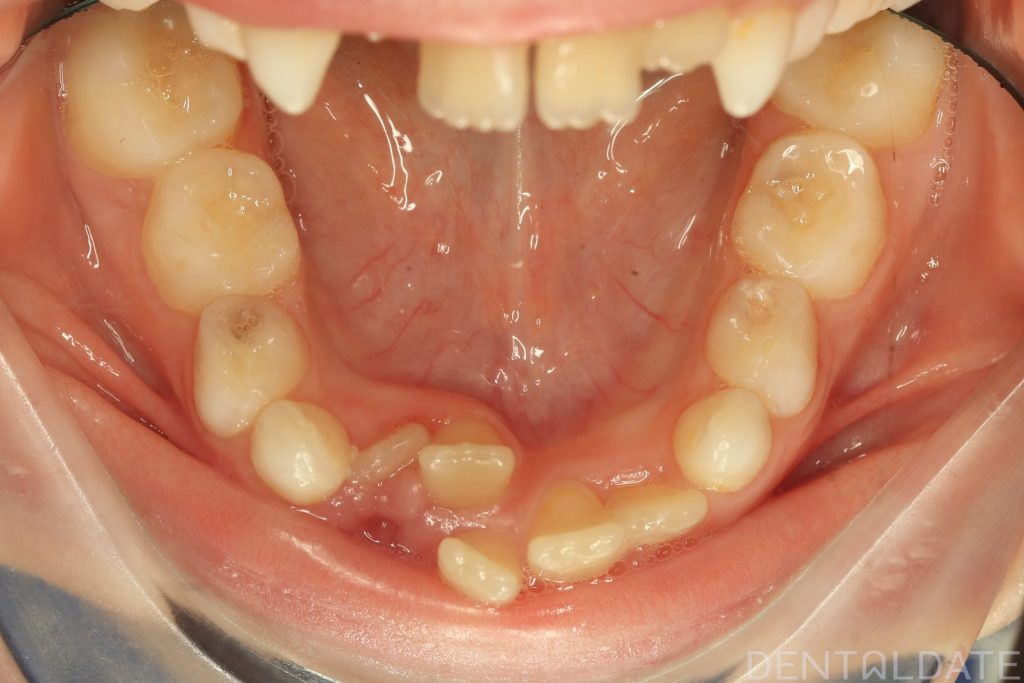

The patient had been undergoing orthodontic treatment at another clinic for 1.5 years with no significant progress.